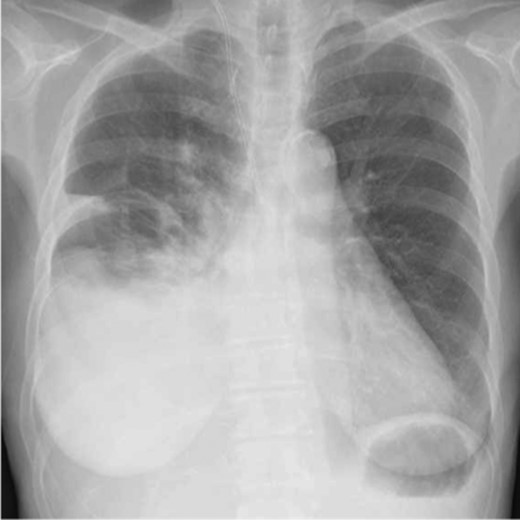

A 70-year-old woman underwent total pancreatectomy for intraductal papillary mucinous neoplasia. Her abdominal drainage tubes were removed on postoperative Days 7 and 8. The ascites volume at that time was not small, but the gastrointestinal surgeons’ policy was to control ascites with diuretics as opposed to drainage; thus, the abdominal drainage tubes were removed. The ascitic fluid was not sent for a biochemical examination. On postoperative Day 12, a chest radiograph showed an acute development of right hydrothorax (Fig. 1). Thoracentesis was performed on postoperative Days 12 and 23. On postoperative Day 23, the pleural fluid was sent for biochemical analysis for the first time. The results showed elevated triglyceride levels (536 mg/dL) and the patient was diagnosed with a right chylothorax. At that time, she had no abdominal symptoms or obvious ascites. After a 1-month long fat-restricted diet and octreotide treatment, the chylothorax was not substantially improved and she was referred to our department.

Chest radiograph on postoperative Day 12 after pancreatectomy A chest radiograph showing a right-sided sub-massive pleural effusion.